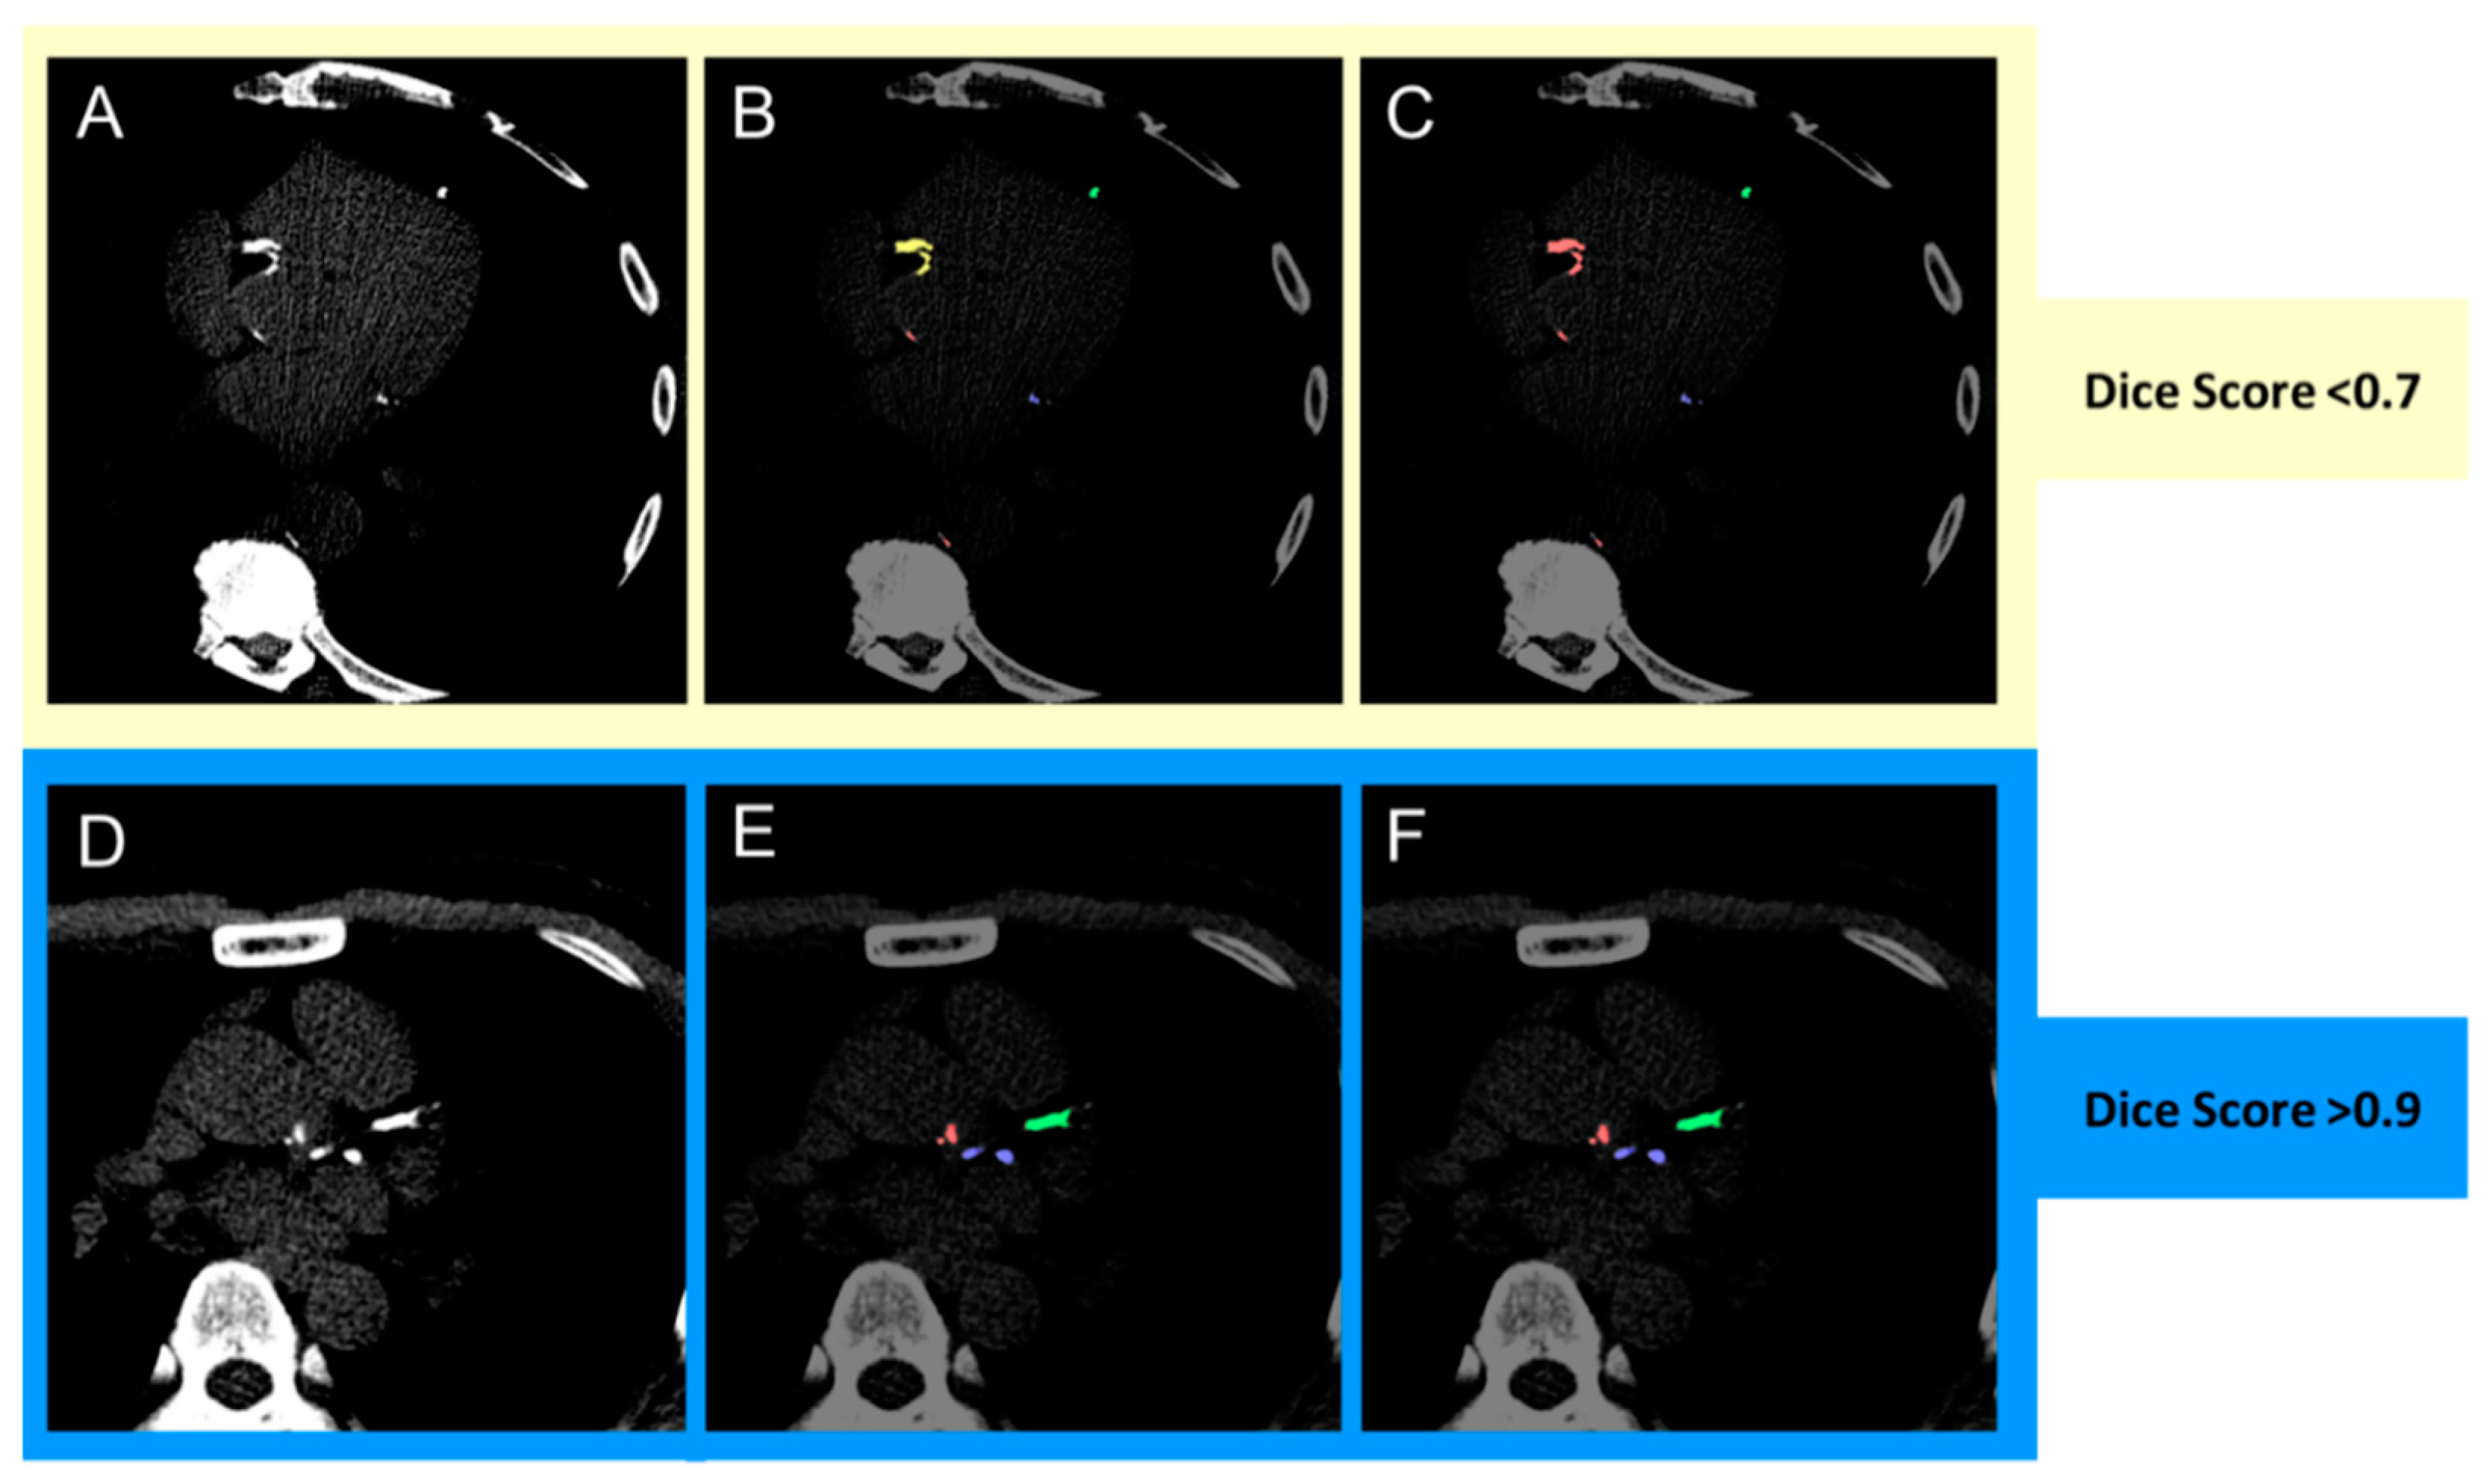

| Total coronary (LAD + RCA + LCx) | Overall | 0.952 | (0.921, 0.981) | - |

| Male | 0.948 | (0.920, 0.981) | 0.350 | |

| Female | 0.965 | (0.933, 0.980) | ||

| Age < 65 years | 0.950 | (0.913, 0.981) | 0.742 | |

| Age ≥ 65 years | 0.957 | (0.930, 0.977) | ||

| LAD | Overall | 0.971 | (0.930, 1.000) | - |

| Male | 0.963 | (0.919, 1.000) | 0.058 | |

| Female | 0.988 | (0.968, 1.000) | ||

| Age < 65 years | 0.970 | (0.941, 0.999) | 0.980 | |

| Age ≥ 65 years | 0.975 | (0.911, 1.000) | ||

| RCA | Overall | 0.963 | (0.889, 0.991) | - |

| Male | 0.951 | (0.880, 1.000) | 0.633 | |

| Female | 0.977 | (0.923, 0.991) | ||

| Age < 65 years | 0.964 | (0.874, 0.999) | 0.875 | |

| Age ≥ 65 years | 0.959 | (0.899, 0.987) | ||

| LCx | Overall | 0.955 | (0.894, 1.000) | - |

| Male | 0.954 | (0.887, 1.000) | 0.388 | |

| Female | 0.958 | (0.942, 0.998) | ||

| Age < 65 years | 0.954 | (0.905, 0.999) | 0.897 | |

| Age ≥ 65 years | 0.955 | (0.887, 1.000) | ||

| Aortic | Overall | 0.832 | (0.759, 0.897) | |

| Male | 0.802 | (0.760, 0.905) | 0.996 | |

| Female | 0.834 | (0.764, 0.883) | ||

| Age < 65 years | 0.833 | (0.776, 0.933) | 0.204 | |

| Age ≥ 65 years | 0.793 | (0.756, 0.862) | ||